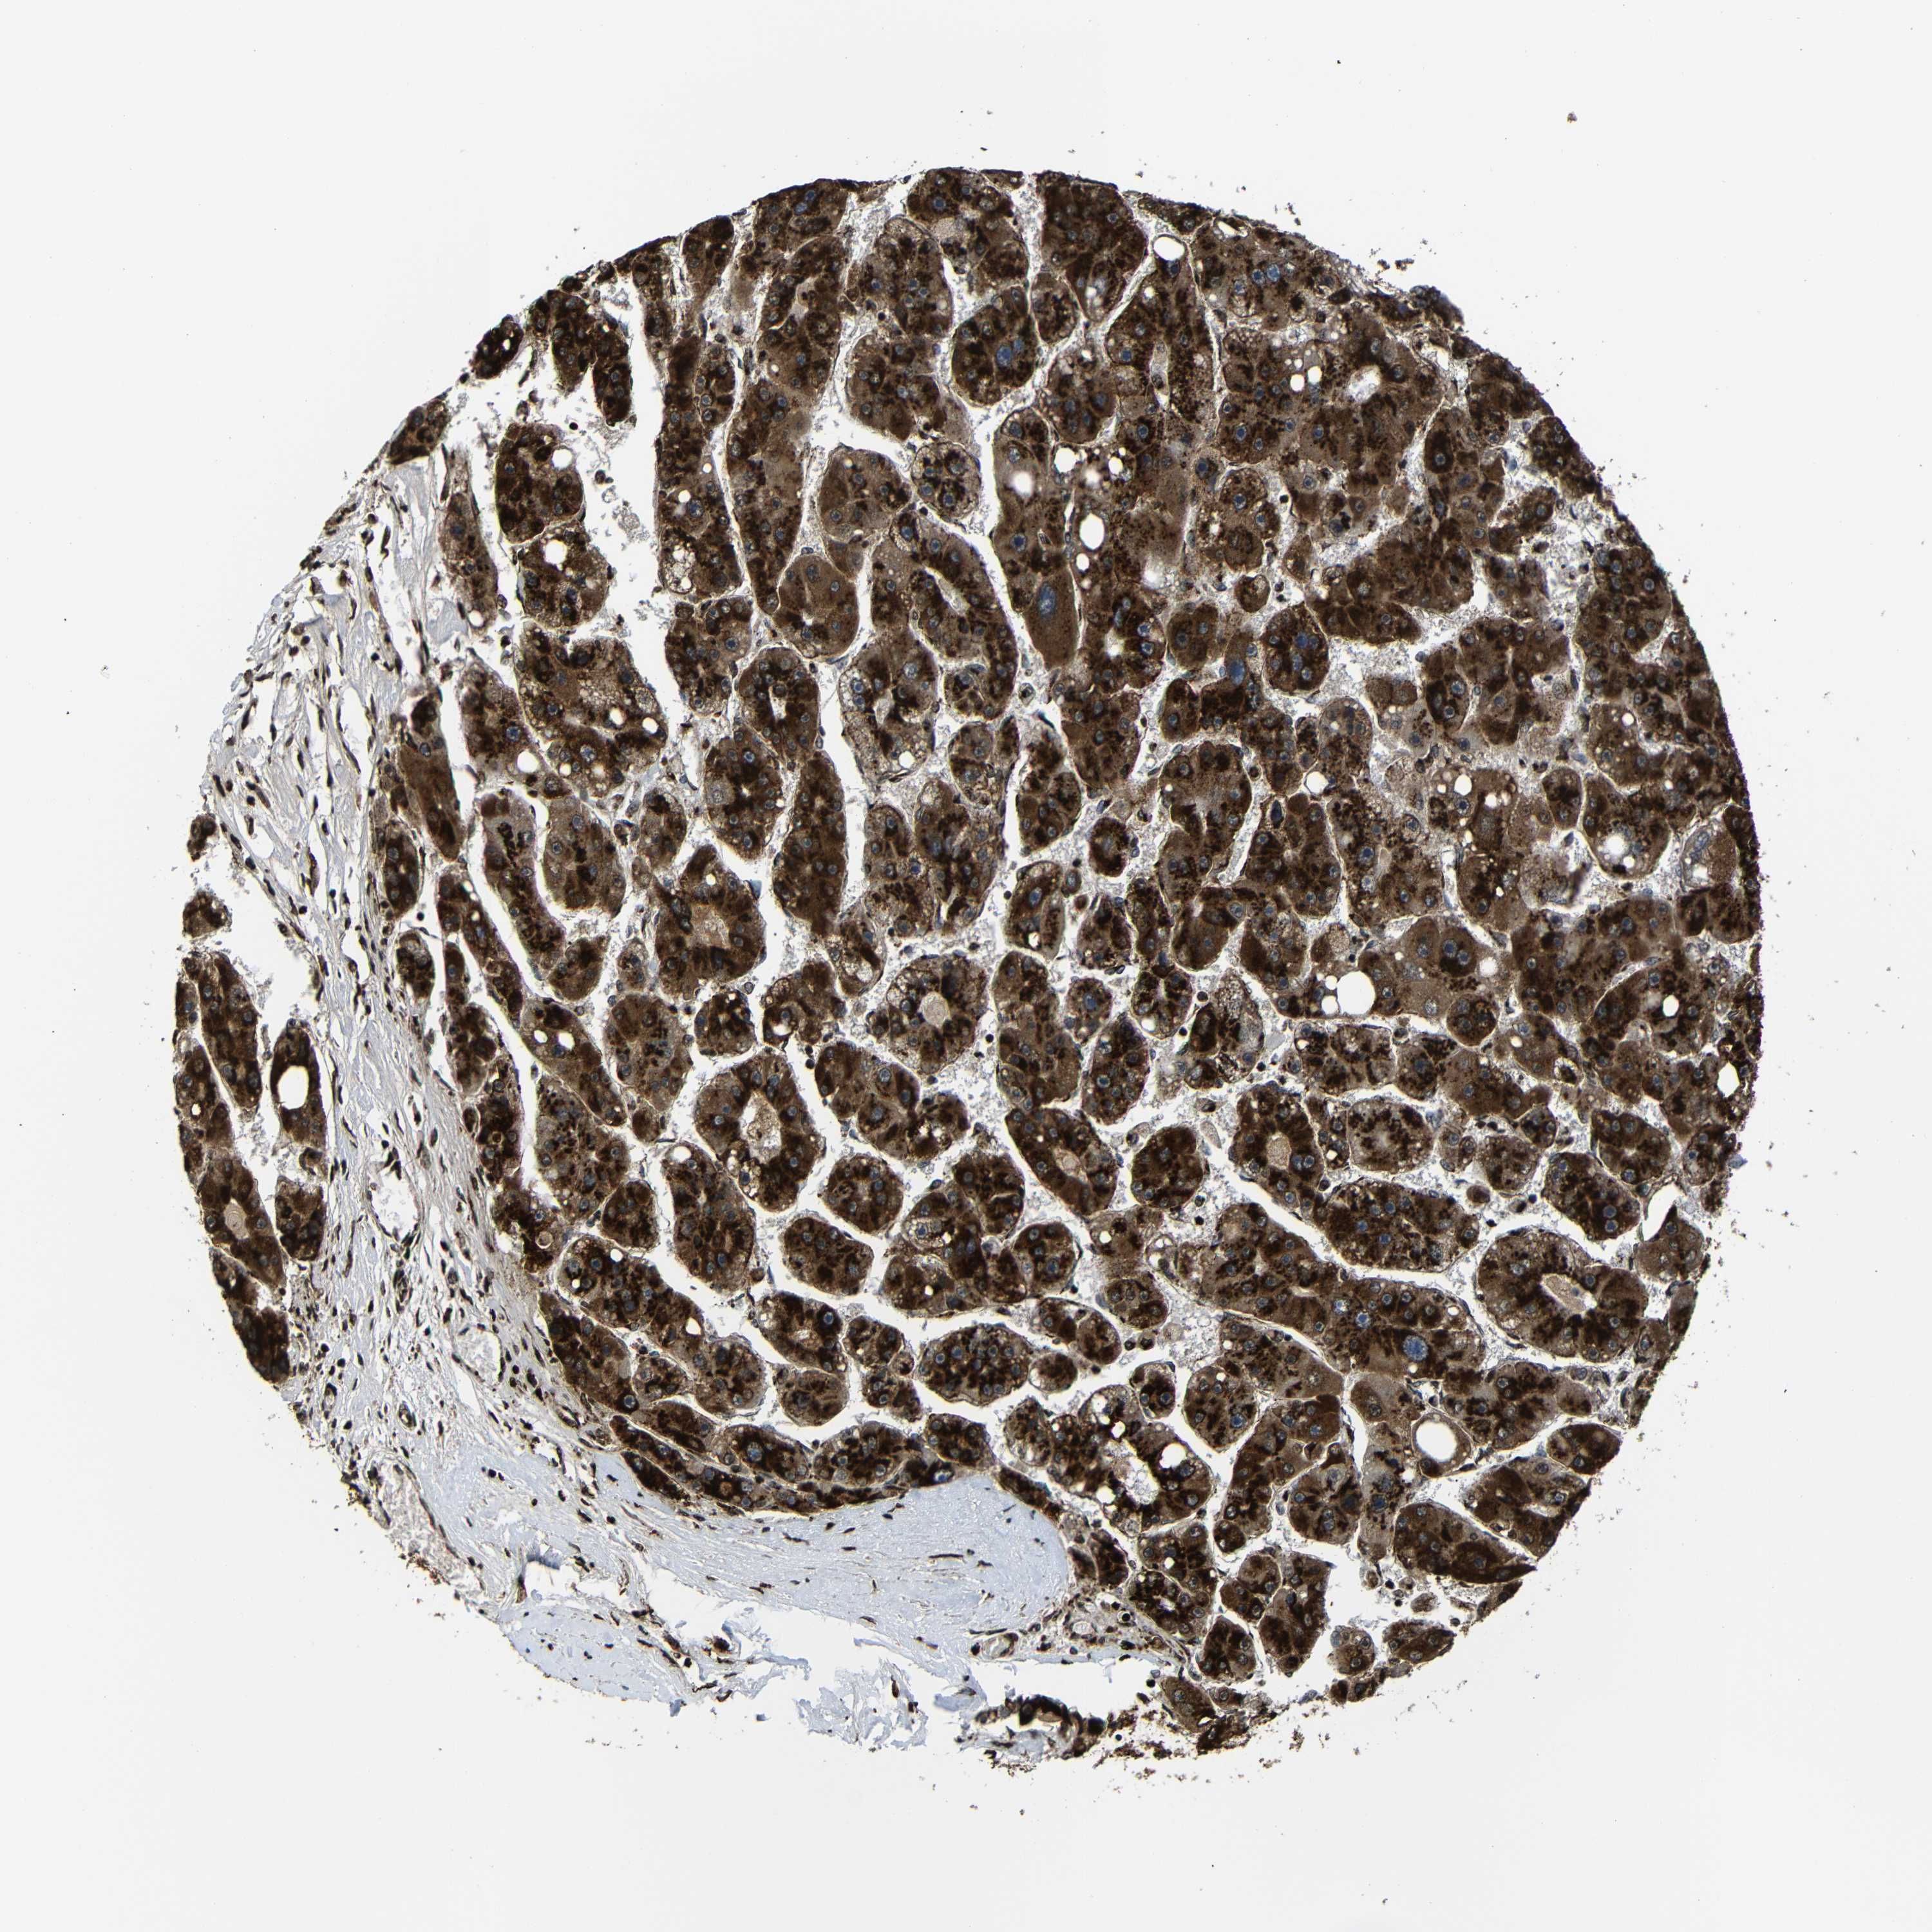

LIVER CANCER - Protein expressioni

A mouse-over function shows sample information and annotation data. Click on an image to view it in a full screen mode. Samples can be filtered based on level of antibody staining by selecting one or several of the following categories: high, medium, low and not detected. The assay and annotation is described here.

Note that samples used for immunohistochemistry by the Human Protein Atlas do not correspond to samples in the TCGA dataset.

Antibody stainingi

Antibody staining in the annotated cell types in the current human tissue is reported as not detected, low, medium, or high, based on conventional immunohistochemistry profiling in selected tissues. This score is based on the combination of the staining intensity and fraction of stained cells.

Each image is clickable and will lead to virtual microscopy that enables deeper exploration of all samples and also displays staining intensity scores, fraction scores and subcellular localization as well as patient and tissue information for each sample.

Antibody HPA012609

Antibody HPA012723

Antibody CAB011489

Staining

High

Medium

Low

Not detected

Intensity

Strong

Moderate

Weak

Negative

Quantity

>75%

75%-25%

<25%

None

Location

Nuclear

Cytoplasmic/membranous

Cytoplasmic/membranous,nuclear

Cholangiocarcinoma

Carcinoma, Hepatocellular, NOS